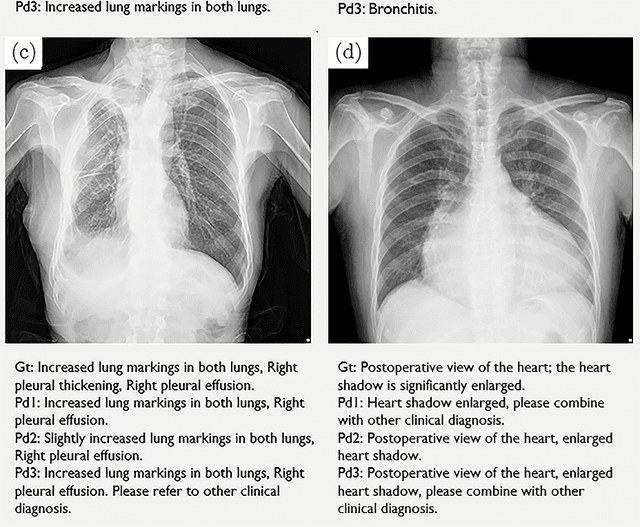

Abstract:The chest X-Ray (CXR) is the one of the most common clinical exam used to diagnose thoracic diseases and abnormalities. The volume of CXR scans generated daily in hospitals is huge. Therefore, an automated diagnosis system able to save the effort of doctors is of great value. At present, the applications of artificial intelligence in CXR diagnosis usually use pattern recognition to classify the scans. However, such methods rely on labeled databases, which are costly and usually have large error rates. In this work, we built a database containing more than 12,000 CXR scans and radiological reports, and developed a model based on deep convolutional neural network and recurrent network with attention mechanism. The model learns features from the CXR scans and the associated raw radiological reports directly; no additional labeling of the scans are needed. The model provides automated recognition of given scans and generation of reports. The quality of the generated reports was evaluated with both the CIDEr scores and by radiologists as well. The CIDEr scores are found to be around 5.8 on average for the testing dataset. Further blind evaluation suggested a comparable performance against human radiologist.